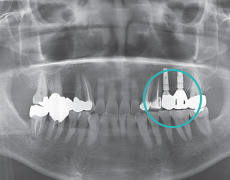

ETAPA 2

ProcedimientoPrimario (Instalación del implante)Posicionamiento de implante en el sitio.

ETAPA 3

Procedimiento Secundario, (Oseointegración y conección de pilar)Conexión del implante y pilart.

ETAPA 4

Rehabilitación ProtésicaInstalación de corona sobre el pilar.